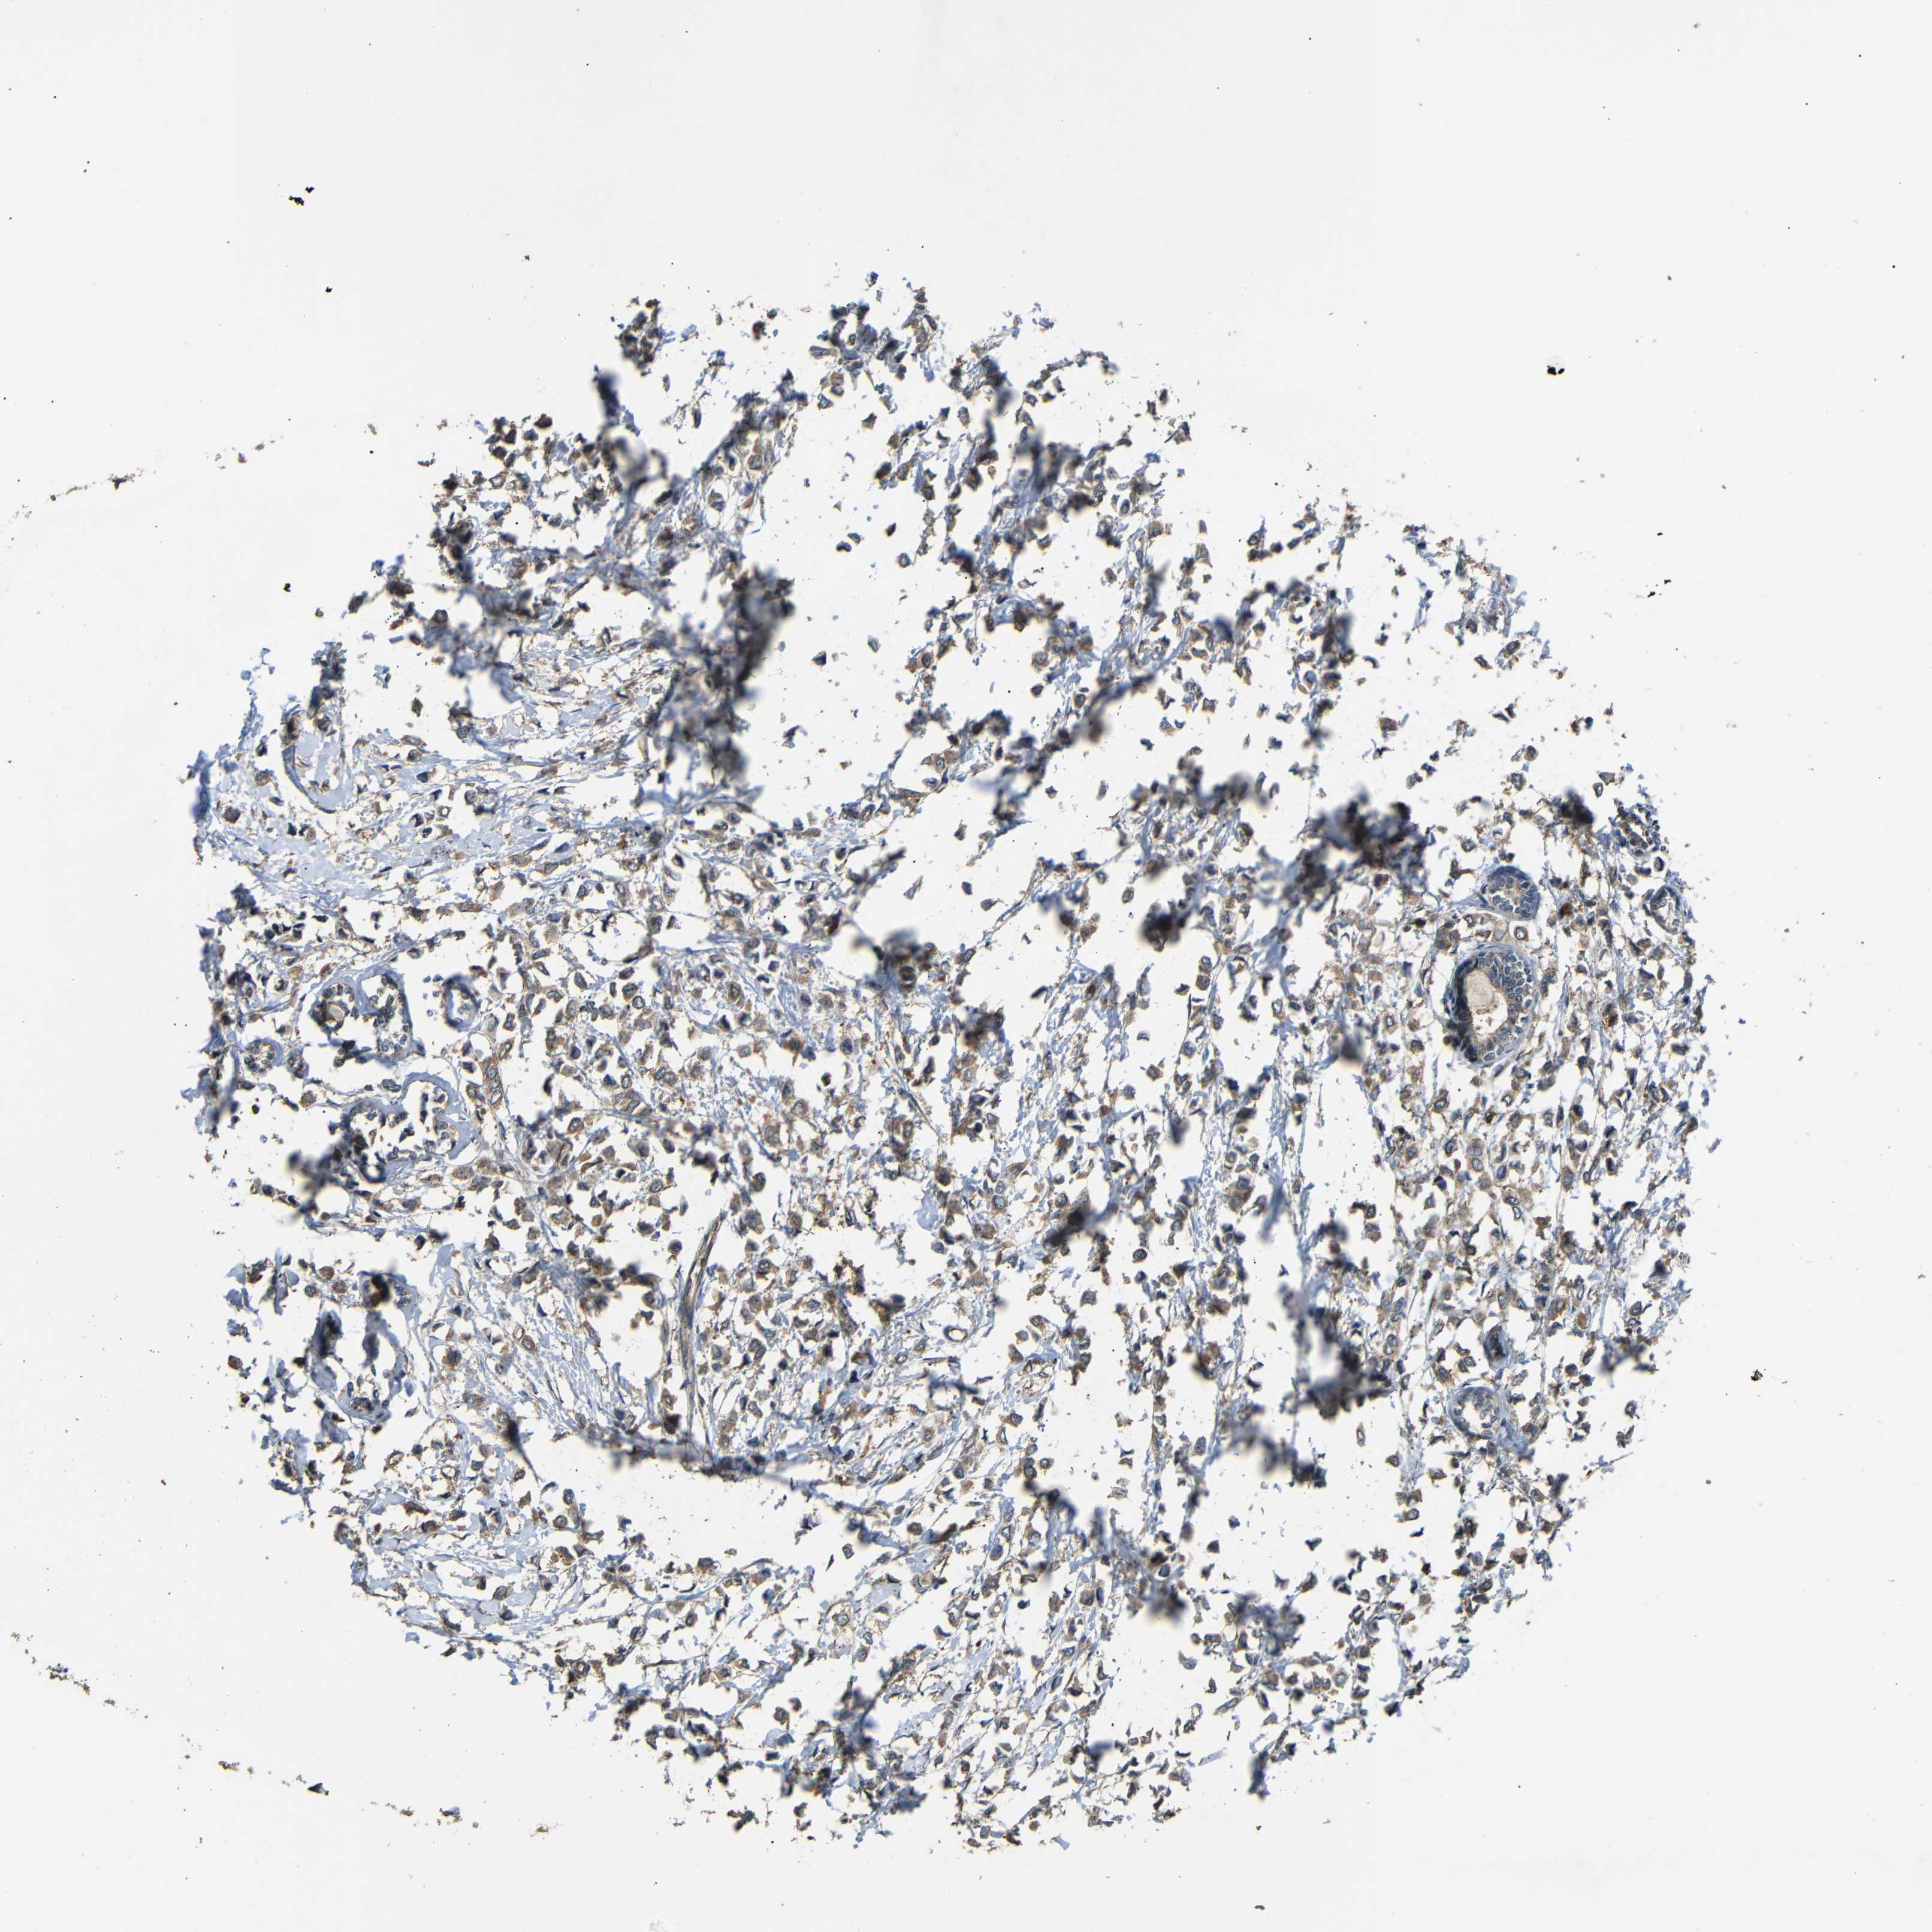

CANCER BREAST CANCER Show tissue menu

BRCA TCGA BRCA VALIDATION PROTEIN EXPRESSION

Breast cancer

Human cancer

Breast invasive carcinoma